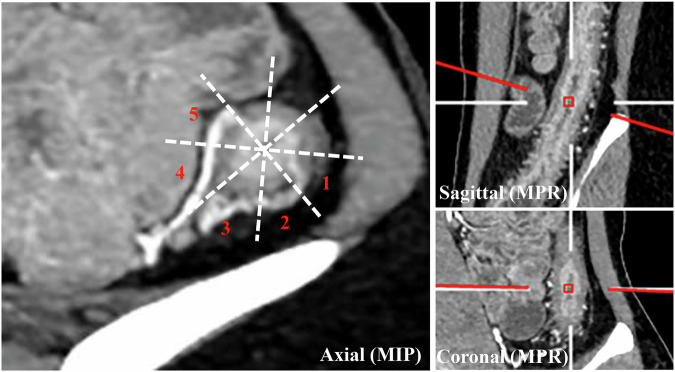

Materials and methods: Adult patients with active CD treated with standard UST from August 2020 to August 2022 were enrolled. Body composition, including creeping fat (CF, mesenteric creeping fat index (MCFI) and fibrofatty proliferation score), skeletal muscle, visceral adipose, and subcutaneous adipose-related parameters were assessed on baseline CTE. Cox regression analysis was performed to identify independent predictors of TH.